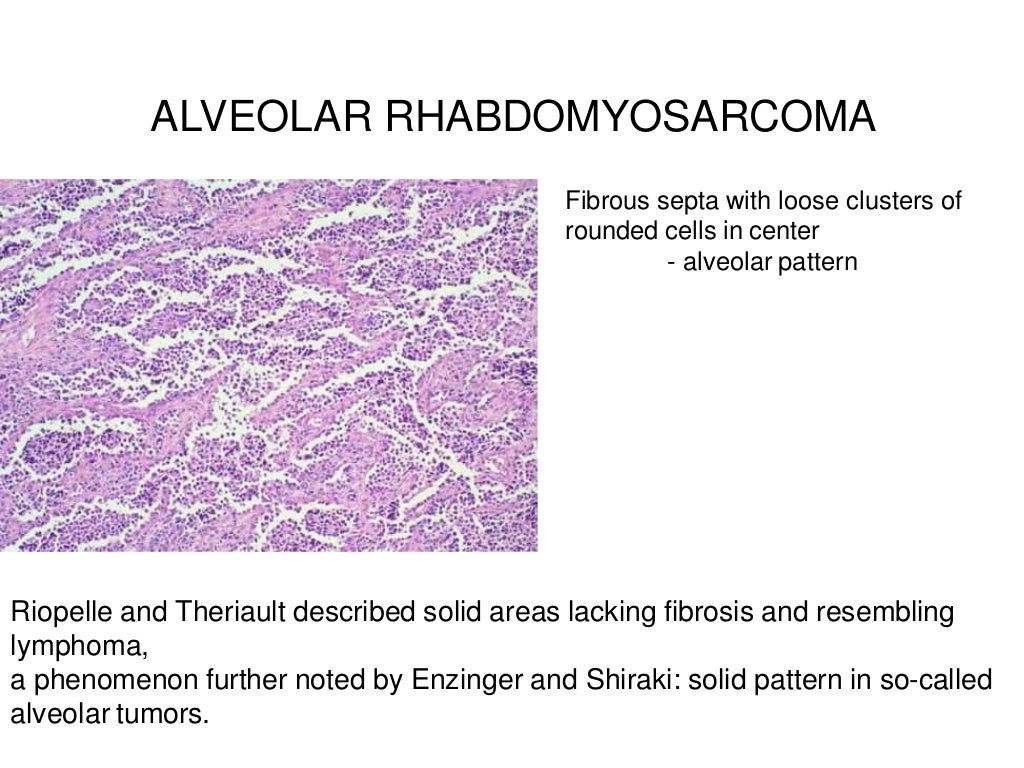

www.slideshare.net

www.slideshare.net

rhabdomyosarcoma alveolar

rhabdomyosarcoma alveolar power pathology low cells sarcoma tumor magnification fig abundant small high